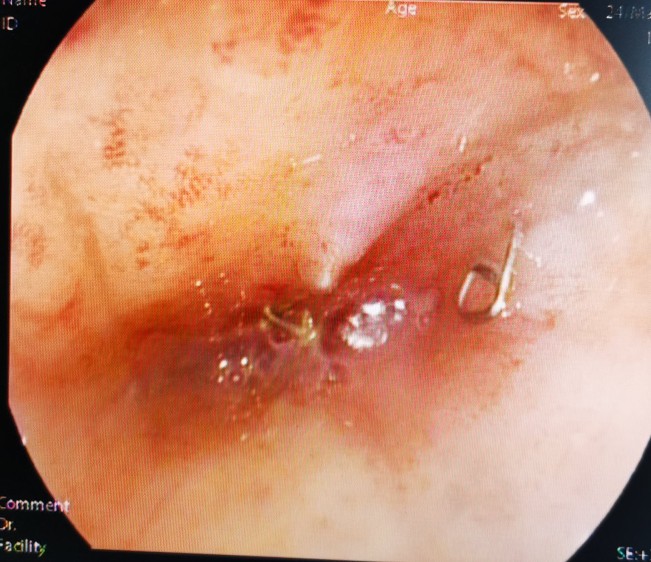

经肛肠镜见吻合口完全闭塞